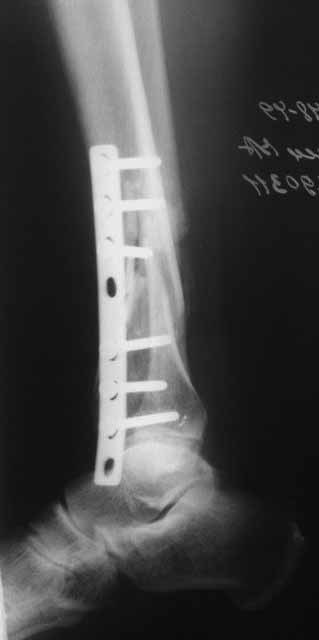

Это гипотрофический ложный сустав. Проблем видится несколько:

1. нарушение трофики в месте перелома.

2. после фиксации в аппарате Илизарова на рентгеногнрамме имеются признаки спицевого остеомиелила. В настоящи момент хотя свищей нет с мая 2011 нет опасно ли фиксировать голень стержнем?

На основании каких признаков Вы решили, что кость мертвая! Имеется гиперпластический ложный сустав, как результат недостаточно стабильной фиксации ан предыдущих этапах лечения. В данном случае необходимо решение следующих вопросов:

Примерная ситуация. Пациент 37 лет. Синтезировали где-то пластинкой. Попал к нам через 2 месяца.

19 апреля убрали через проколы пластину с винтами, пересекли fibula, наложили аппарат.

Немного потянули по оси, убрали вальгус, ротацию. 22 апреля (на 3-е сутки) заштифтовали окончательно. 29 апреля выписали из отделения. На все ушло 10 дней.

Место ложного сустава не выглядит гипертрофическим. Нет разрастания костной мозоли.